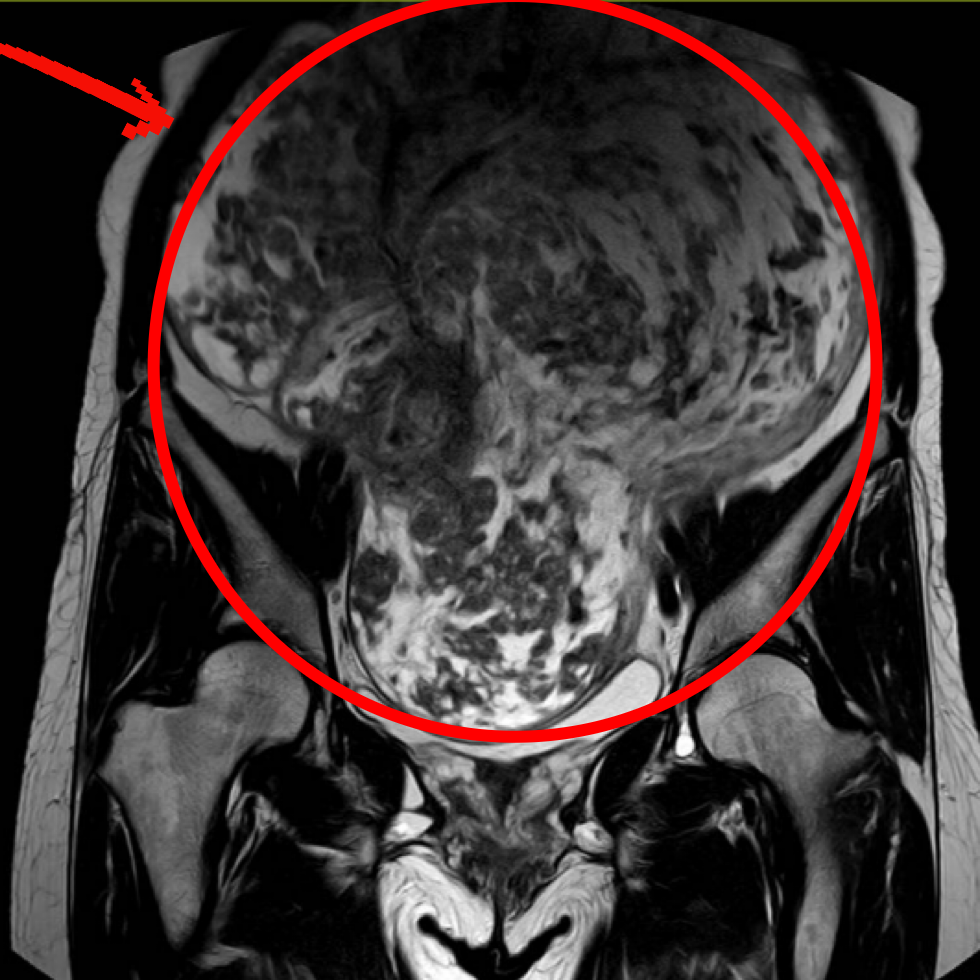

核磁共振进一步确认,这个肿块大小约28×18.58×34.8(厘米3),像冬瓜一样大,边界清晰,上顶横膈膜,下撑骨盆底,没有扩散迹象。

洪女士的核磁共振图像